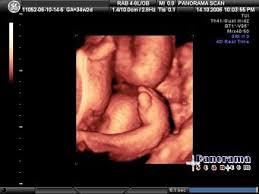

Imaging technique and findings ultrasound. Five cases of congenital clubfoot diagnosed prenatally by ultrasound are reported. Congenital talipes equinovarus is considered the most common anomaly affecting the feet diagnosed on antenatal ultrasound. The addition of microarray studies may increase the yield of invasive prenatal testing, although the complex inheritance patterns of clubfoot suggest that it rarely occurs due to a single gene mutation. 44% of fetuses underwent invasive diagnostic testing. Approximately 10% of all clubfeet can be diagnosed by 13 weeks gestation, and about 80% can be diagnosed by 24 weeks gestation. Although clubfoot is diagnosed at birth, many cases are first detected during a prenatal ultrasound. Ility of the ponseti method in correcting clubfeet; Once the child is born, the condition is clearly visible. Clubfoot can also be diagnosed by a doctor immediately after a baby is born. About 10 percent of clubfeet can be diagnosed as early as 13 weeks into pregnancy. Clubfoot may also result from a restricted environment in utero, such as from prolonged oligohydramnios or with abnormalities of the uterus that limit expansion of the gestational sac. Prenatal diagnosis of clubfoot is made sonographically when the bones of the foot lie in the same planes as the bones of the lower leg (figure 1).

In a fetus with clubfoot, the long axis of the foot (the sole) and the tibia can be seen in the same plane on ultrasound. However, diagnosis based on ultrasound alone produces a 20% false positive rate. Clubfoot is present in approximately 1 in 1000 live births in the united states. As many as four children out of every 1,000 are born with clubfoot. About 50 percent of children with clubfoot have it in both feet, a condition known as bilateral clubfoot.

About 10 percent of clubfeet can be diagnosed as early as 13 weeks into pregnancy. The incidence of clubfoot may be higher within an affected family and may be associated with other structural anomalies or chromosomal abnormalities. Like about half of children with the condition, the ultrasound showed that cheryl and sue's baby would have clubfeet on both sides. Approximately 10% of all clubfeet can be diagnosed by 13 weeks gestation, and about 80% can be diagnosed by 24 weeks gestation. Clubfoot, or talipes equinovarus, refers to a developmental deformity of the foot in which one or both feet are excessively plantar flexed, with the forefoot swung medially and the sole facing inward ().it is a common congenital malformation, typically discovered at the time of birth as an isolated anomaly in an otherwise normal neonate. Questions and fears about clubfoot diagnosis. And (2) determine whether various ultrasound (us) variables correlated with each other and with the pirani score before and after treatment. The condition is normally identified after birth, but doctors can also tell if an unborn baby has.